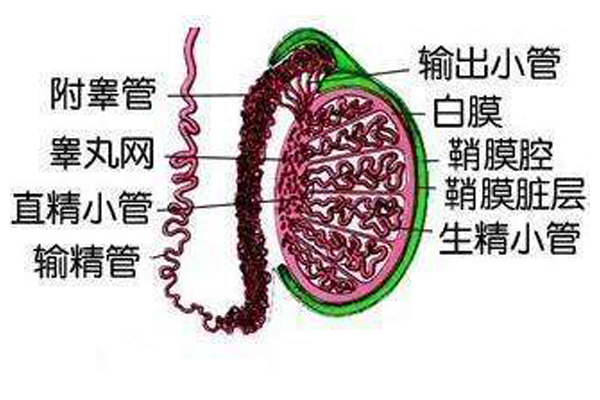

输精管畸形会对男性生育能力产生非常恶劣的影响,通常需要明确病因,对症治疗。不过多数患者仍有生育需求,可以考虑二代试管婴儿治疗(ICSI)来解决男性生育方面的问题。...

成功治疗无精症男性患者,并使其成为某个孩子遗传学上的父亲,这是过去20年来不育治疗领域中取得的最引人注目的进展。对于无精症患者来说,使用捐赠者精子早已不再是第一位...

所有不孕症中约有40%是由男性因素引起的。精液分析是评估男性因素的主要测试手段。精液分析内容包括体积,液化时间,白血细胞(检查是否有感染)评估,精子的数量或浓度时...

调查显示:在整个不孕不育的人群中,有明确男性因素的约占48%。导致男性不育的病因有很多,包括内分泌因素、遗传因素、环境因素,甚至还有60%左右是不明原因的,即特发...